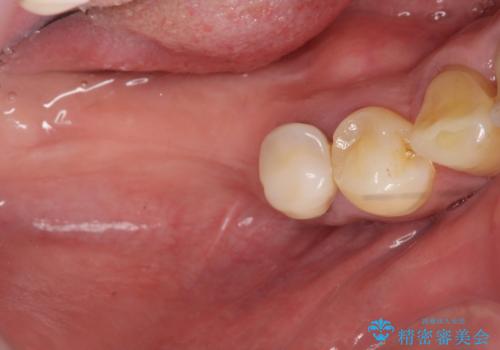

長期的な予後の見込めない奥歯の抜去を行い、骨と歯ぐきの治癒を待ち、インプラント治療を計画します。

インプラント周囲には骨の増生を埋入時に同時に行っています。